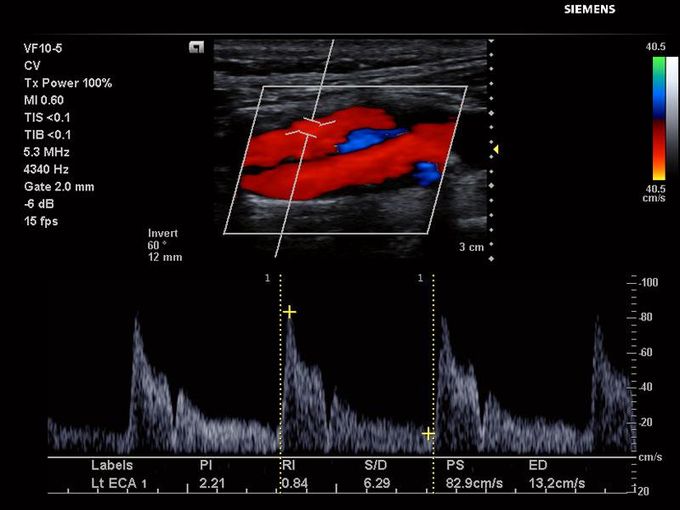

Кроме новой техники, можно заказать восстановленные медицинские системы: ультразвуковые сканеры, томографы, флюороскопы, ангиографы и хирургические установки С-дуга.